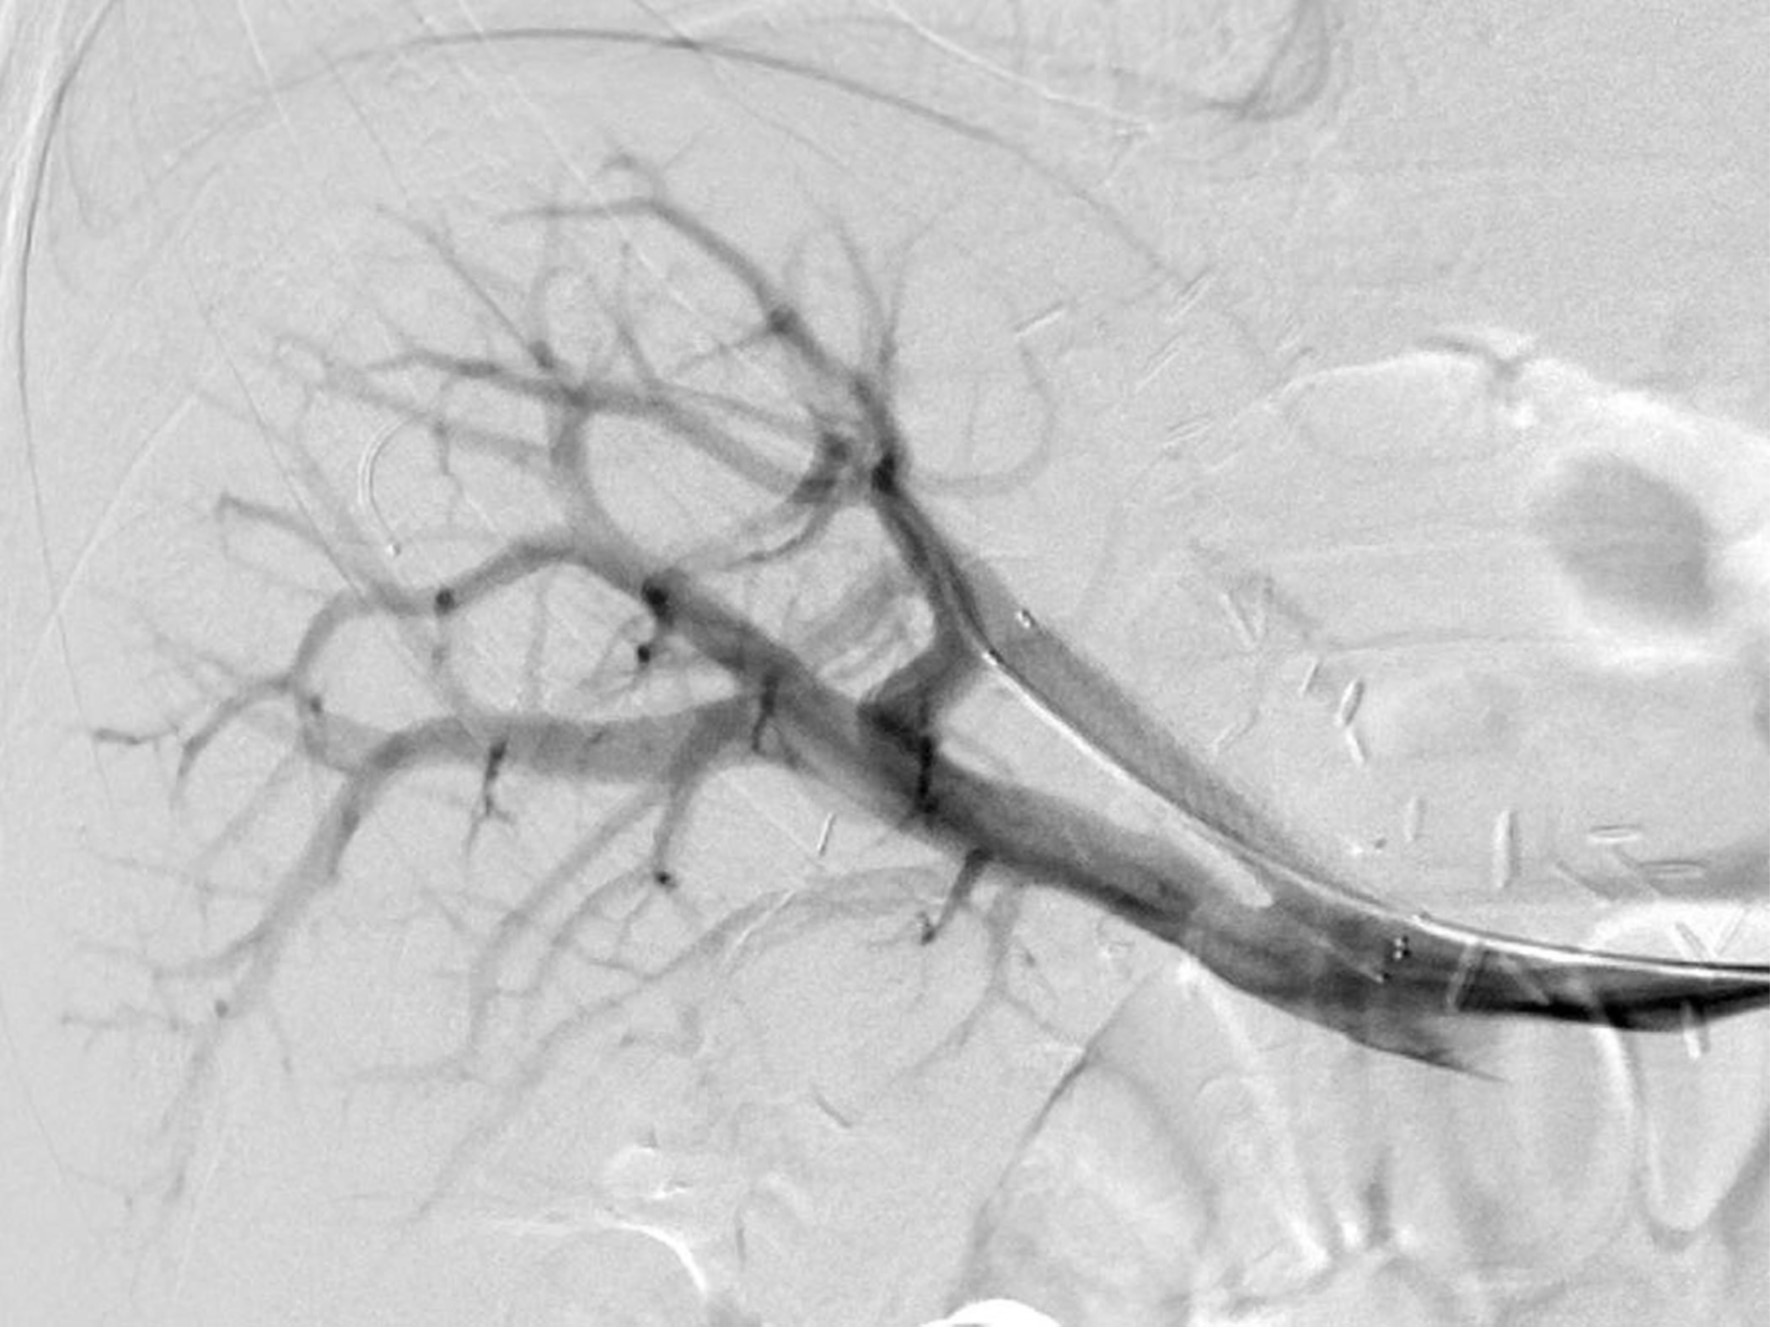

초음파 유도하에 비장정맥(splenic vein)을 천자하여, 8Fr sheath를 삽입하였음. Sheath를 통한 간문맥조영술(splenoportography)에서, 우전문맥(right anterior portal vein)의 심한 협착을 확인하였음(Fig. 2A). 이후 guidewire를 사용하여 우전문맥을 선택한 뒤, 6x40mm의 Stent(Zilver; Cook Medical, Bloomington, IN)를 삽입하였고, 남은 병변에 대해서 6x40mm balloon(Ultrathin Diamond;Boston Scientific, Natric, MA)을 이용하여 혈관성형술을 시행하였음. 이후 시행한 간문맥 조영술(Portal venography)에서 협착의 호전을 확인할 수 있었음(Fig. 2B). 삽입한 sheath의 지혈을 위해서, Histoacry(N-butyl-cyanoacrylate, B.Braun,Germany)과 lipiodol(Lipiodol Ultrafluid, Andre Guerbet, Aulnay-sous-bois, France)의 혼합(mixture, 1:4) 2cc로 tract embolization한 후 시술을 종료하였음.

Fig. 2. A

Fig. 2A Splenoportography shows severe stenosis of right ant. Portal vein(arrow).